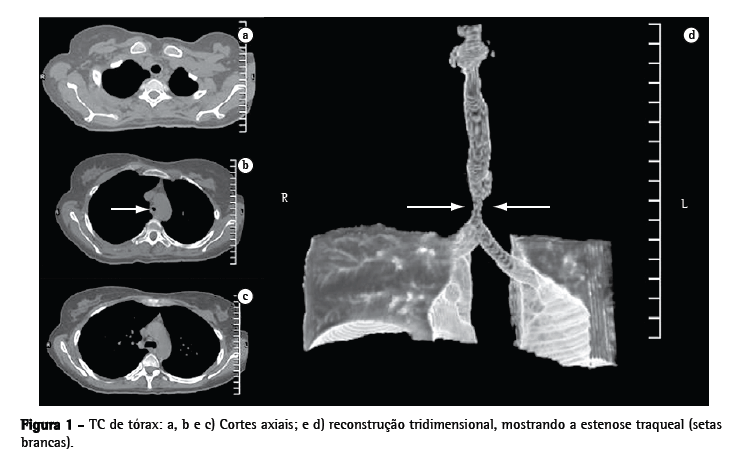

Ao exame físico apresentava estridor, além de roncos difusos. O radiograma de tórax evidenciava diminuição significativa da coluna aérea na topografia da traquéia distal. A tomografia computadorizada (TC) do tórax com reconstrução tridimensional (Figura 1) evidenciou estenose da traquéia distal (com extensão de 15 mm) 20 mm acima da carina traqueal.

A TC da via aérea foi realizada no 3º dia de pósoperatório (com retirada momentânea do TOT sob visão endoscópica), sendo obtidas as dimensões da traquéia estenosada. Tanto a reconstrução tridimensional da traquéia como suas medidas foram encaminhadas a Hood Laboratories (Pembroke, MA, EUA). Com base nessas dimensões, foi adquirida uma prótese traqueobrônquica siliconizada (tipo T-Y), compatível com a via aérea da paciente (Figura 2).

Estudos de imagem devem preceder a endoscopia respiratória, servindo inclusive para orientar sua realização. Esses exames auxiliam na avaliação da via aérea distal à estenose naqueles casos em que não é possível a passagem do endoscópio pela estenose. Este achado é decisivo no planejamento cirúrgico. Os estudos de imagem também desempenham um papel importante no diagnóstico de lesões algumas vezes de difícil percepção na broncoscopia, como a presença de malácia.(8) A TC com reconstrução oferece ótima acurácia no diagnóstico de estenose traqueobrônquica, incluindo a localização anatômica, o número de lesões presentes e o status da via aérea distal à lesão. Alguns autores,(9) estudando pacientes com estenose traqueobrônquica, observaram uma sensibilidade de 100% da TC com reconstrução.